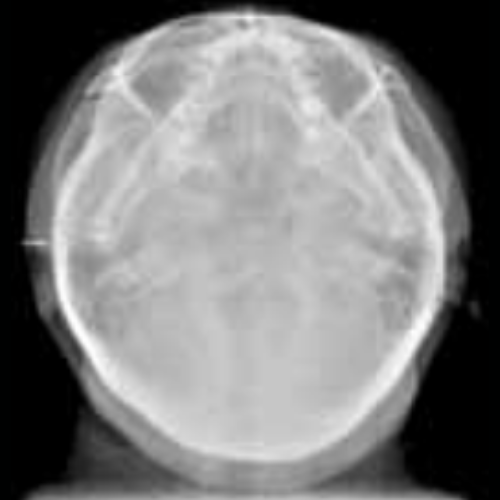

The Vatech PaX-i3D Green panoramic plus cone beam system delivers large field of view (up to 15 x 15 cm) dental CBCT scans in addition to standard 2D panorex and extraoral bitewing X-ray images. This Vatech CBCT machine features the innovative green CT technology which minimizes patient dose, while the Rapid Scan feature delivers high-quality 3D cone beam scans in just 5.9 seconds. A quick exposure time helps to minimize artifacts and motion, while at the same time reducing patient dose, making your imaging process more efficient and safer.

- Cephalometric